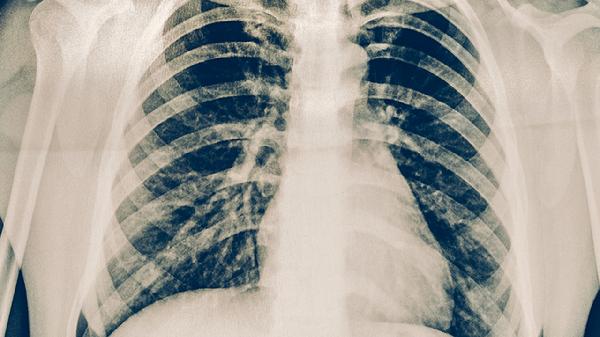

肺结核患者的营养原则

肺结核患者的营养原则主要包括高热量、高蛋白、高维生素、适量矿物质和充足水分摄入。合理的营养支持有助于改善患者免疫功能,促进病灶修复,减少药物不良反应。